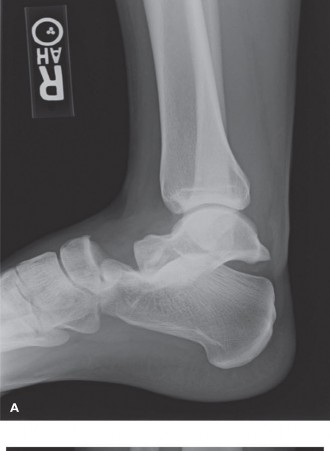

A 28-year-old man falls from a ladder at work from approximately 12 feet, injuring his right ankle. He is tak…